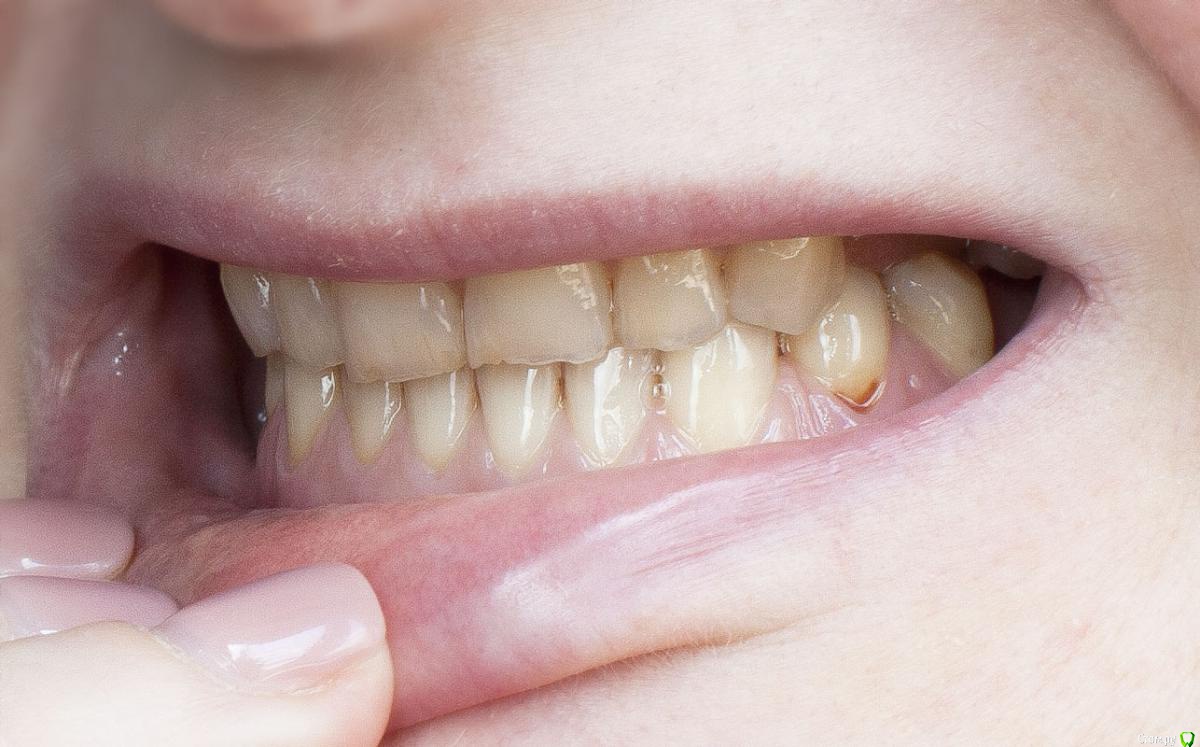

Barbar Опубликовано 21 июля, 2015 Автор Поделиться Опубликовано 21 июля, 2015 что именно Вам мешает широко улыбаться??? форма зубов, их расположение, отсутствие боковых зубов...? что именно Вы хотели справить с помощью брекетов? Вам стоматолог посоветовал заниматься прикусом или это Ваши предположения? если хотите просто поставить отсутствующие зубы - то Вам к ортопеду надо. Он посмотрит и скажет , ДОСТАТОЧНО ли места по ширине и высоте для имплантации и протезирования. если да, то просто протезируйтесь. Если же нет - то тогда Вам к ОРТОДОНТУ. Да, да и да! " форма зубов, их расположение, отсутствие боковых зубов..."Ладно, их расположение устраивает, во рту они как раз на правильном месте %РМне не нравится, что зубы пожелтели, неровны и сточены, особенно нижние. И прикус!Верхние зубы направлены немного вовнутрь и перекрывают нижние, у которых от этого сильный наклон вовнутрь. Уж не знаю как лучше объяснить, я не врач и терминами не владею. Думала, что всё понятно по фото. Улыбка получается жалкая. Имплантаты на место отсутствующих зубов будут ставить, уже решено. 6 штук, что недёшево. Но хотелось наконец решить эту проблему так, чтобы не было мучительно... то есть все продумать и закрыть тему зубов на долгие годы. Исправить прикус тоже.Мои вопросы были - с чего начать? Какие варианты? Помогут ли (для прикуса) просто коронки на передние нижние зубы? тогда придётся закрыть коронками весь ряд? или только 6 зубов? Или поставить имплантаты и постепенно исправлять прикус лигвальными брикетами? Но тогда высота имплантатов после исправления будет недостаточной? Ссылка на комментарий

Barbar Опубликовано 23 июля, 2015 Автор Поделиться Опубликовано 23 июля, 2015 И причём безо всяких брикетов. По сценарию: пришла, заснула, очнулась - мне зубы, а ему деньги. Я думаю, это мечта любого стоматолога (прошу не обижаться, это добрая шутка)По поводу эстетики - вам правда мои зубы кажутся в полном порядке или просто у вас мои фото в полный размер не открываются? На последней фотографии особенно видно, что нижние зубы сточены и пожелтели, а верхние неровные, имеют зазубренные края и частично уже прозрачные, или нет? Вы, как стоматолог, можете видеть проблемы в зубах, кажущихся идеальными, что простым смертным не под силу, и при этом мои зубы Вам кажутся вполне эстетичными? Ссылка на комментарий

Yana guapa Опубликовано 23 июля, 2015 Поделиться Опубликовано 23 июля, 2015 По поводу эстетики - вам правда мои зубы кажутся в полном порядке или просто у вас мои фото в полный размер не открываются? На последней фотографии особенно видно, что нижние зубы сточены и пожелтели, а верхние неровные, имеют зазубренные края и частично уже прозрачные, или нет? Вы, как стоматолог, можете видеть проблемы в зубах, кажущихся идеальными, что простым смертным не под силу, и при этом мои зубы Вам кажутся вполне эстетичными?многие пациенты позавидовали бы Вашим зубам )) пусть и боковые Вы по каким то причинам потеряли , но передние зубы здоровые.немного стерлись режущие края (но вы не забывайте что и со временем у всех людей стираются зубы, ну и конечно Вы их повышенно истирали в связи с отсутствием боковых зубов). их можно заполировать просто. Я так понимаю что все-таки Вас больше беспокоит непосредственно расположение зубов, степень их обнажения при улыбке - это тогда исправлять только брекетами. Вообще - улыбку нужно уметь носить и преподносить!)) Возможно можно ее дополнительно оформить, например, сделать губы немного пухлее, тогда вся улыбка станет выразительнее. как вариант - подумайте) Ссылка на комментарий